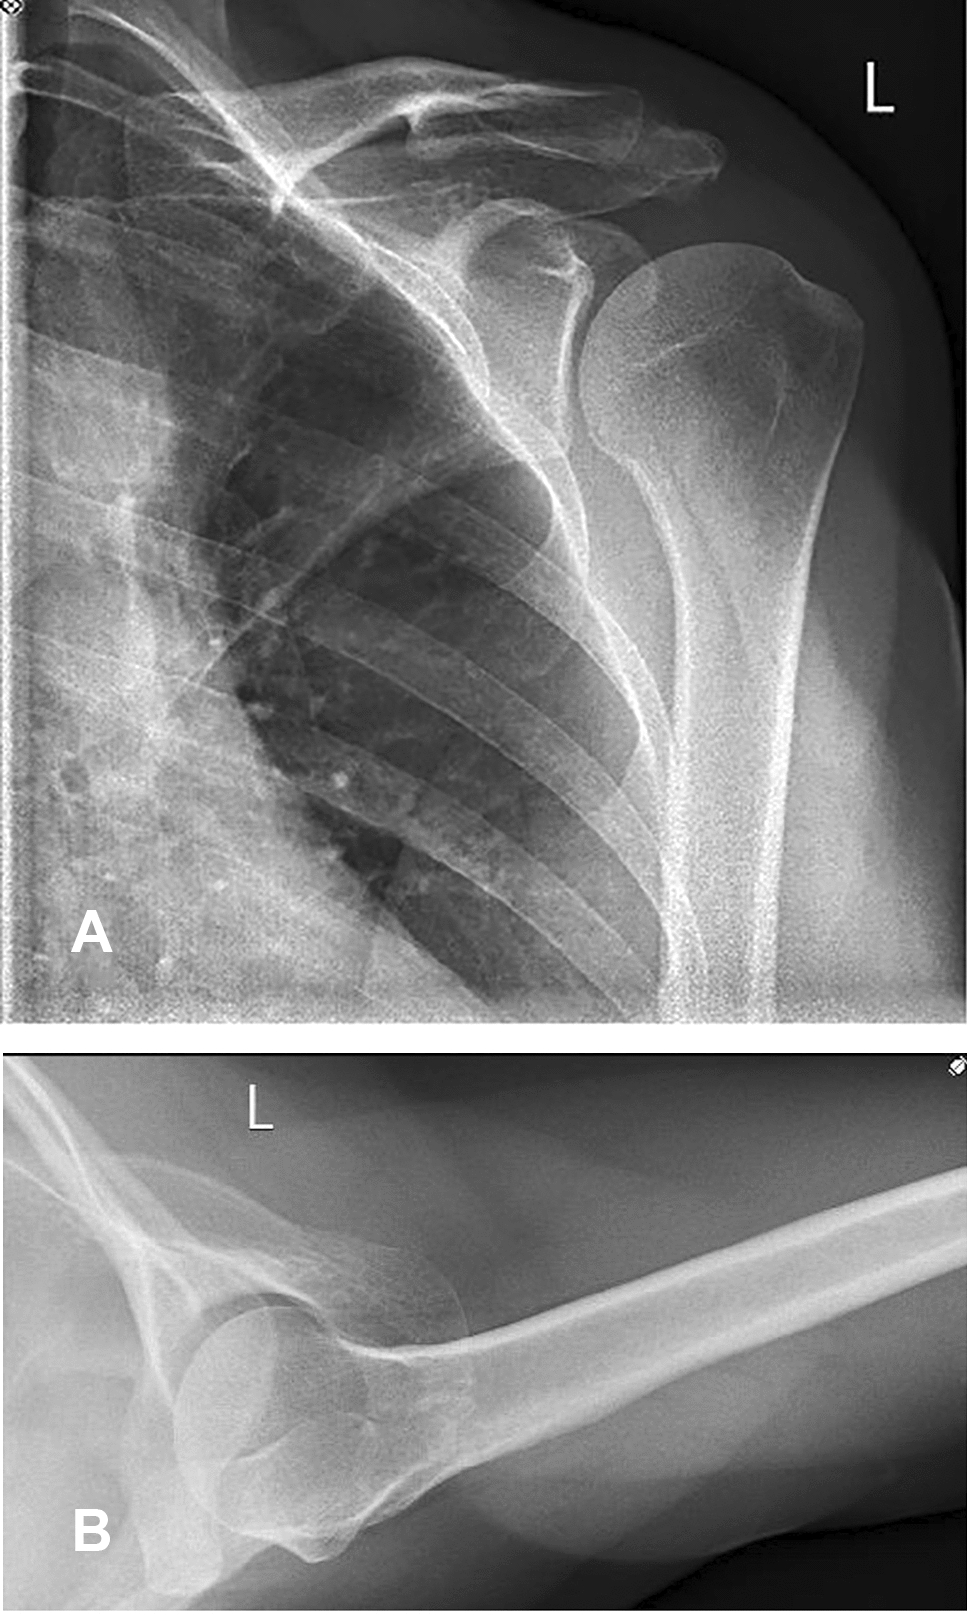

Clinical examination revealed tenderness and pain above the acromial region with a positive impingement sign according to Neer [14]. Active and passive range of motion could be performed without any restrictions. Conventional radiographs and magnetic resonance imaging depicted an os acromiale indicated by a 2.5 cm long fragment in connection with the acromioclavicular joint and additional inflammation of the subacromial bursa (Figs. 1 and 2).

Fig. 1

AB Preoperative anteroposterior and axillary view radiographs